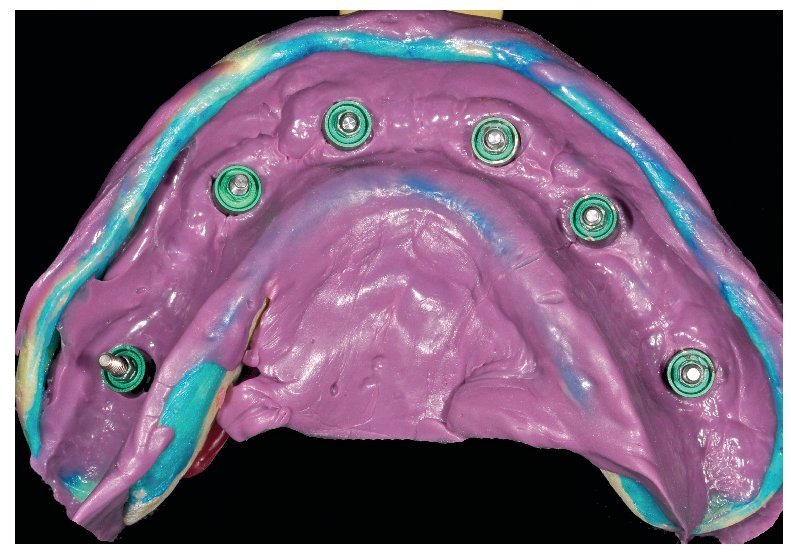

Tras una fase de curación sin complicaciones, se esperaron otros dos meses antes de ajustar las prótesis provisionales a las condiciones ahora estables de la mucosa. Se rebasaron los espacios intermedios formados a causa de la detumescencia del tejido blando tras la intervención, a fin de reducir o incrementar el volumen del cuerpo de la prótesis conforme a las indicaciones funcionales, higiénicas, fonéticas y estéticas, así como teniendo permanentemente en cuenta la oclusión. Una vez concluida esta fase pueden tomarse las impresiones para la restauración definitiva (figs. 75 a 79). Para la restauración de puente planificada, se toman las impresiones a nivel del implante.

Fig. 76. La toma de impresión definitiva en el maxilar superior tiene lugar a la altura del hombro del implante.

Fig. 77. La toma de impresión definitiva en el maxilar inferior tiene lugar a la altura del hombro del implante.

Fig. 78. Vista detallada de la impresión del maxilar superior.

Fig. 79. Vista detallada de la impresión del maxilar inferior.